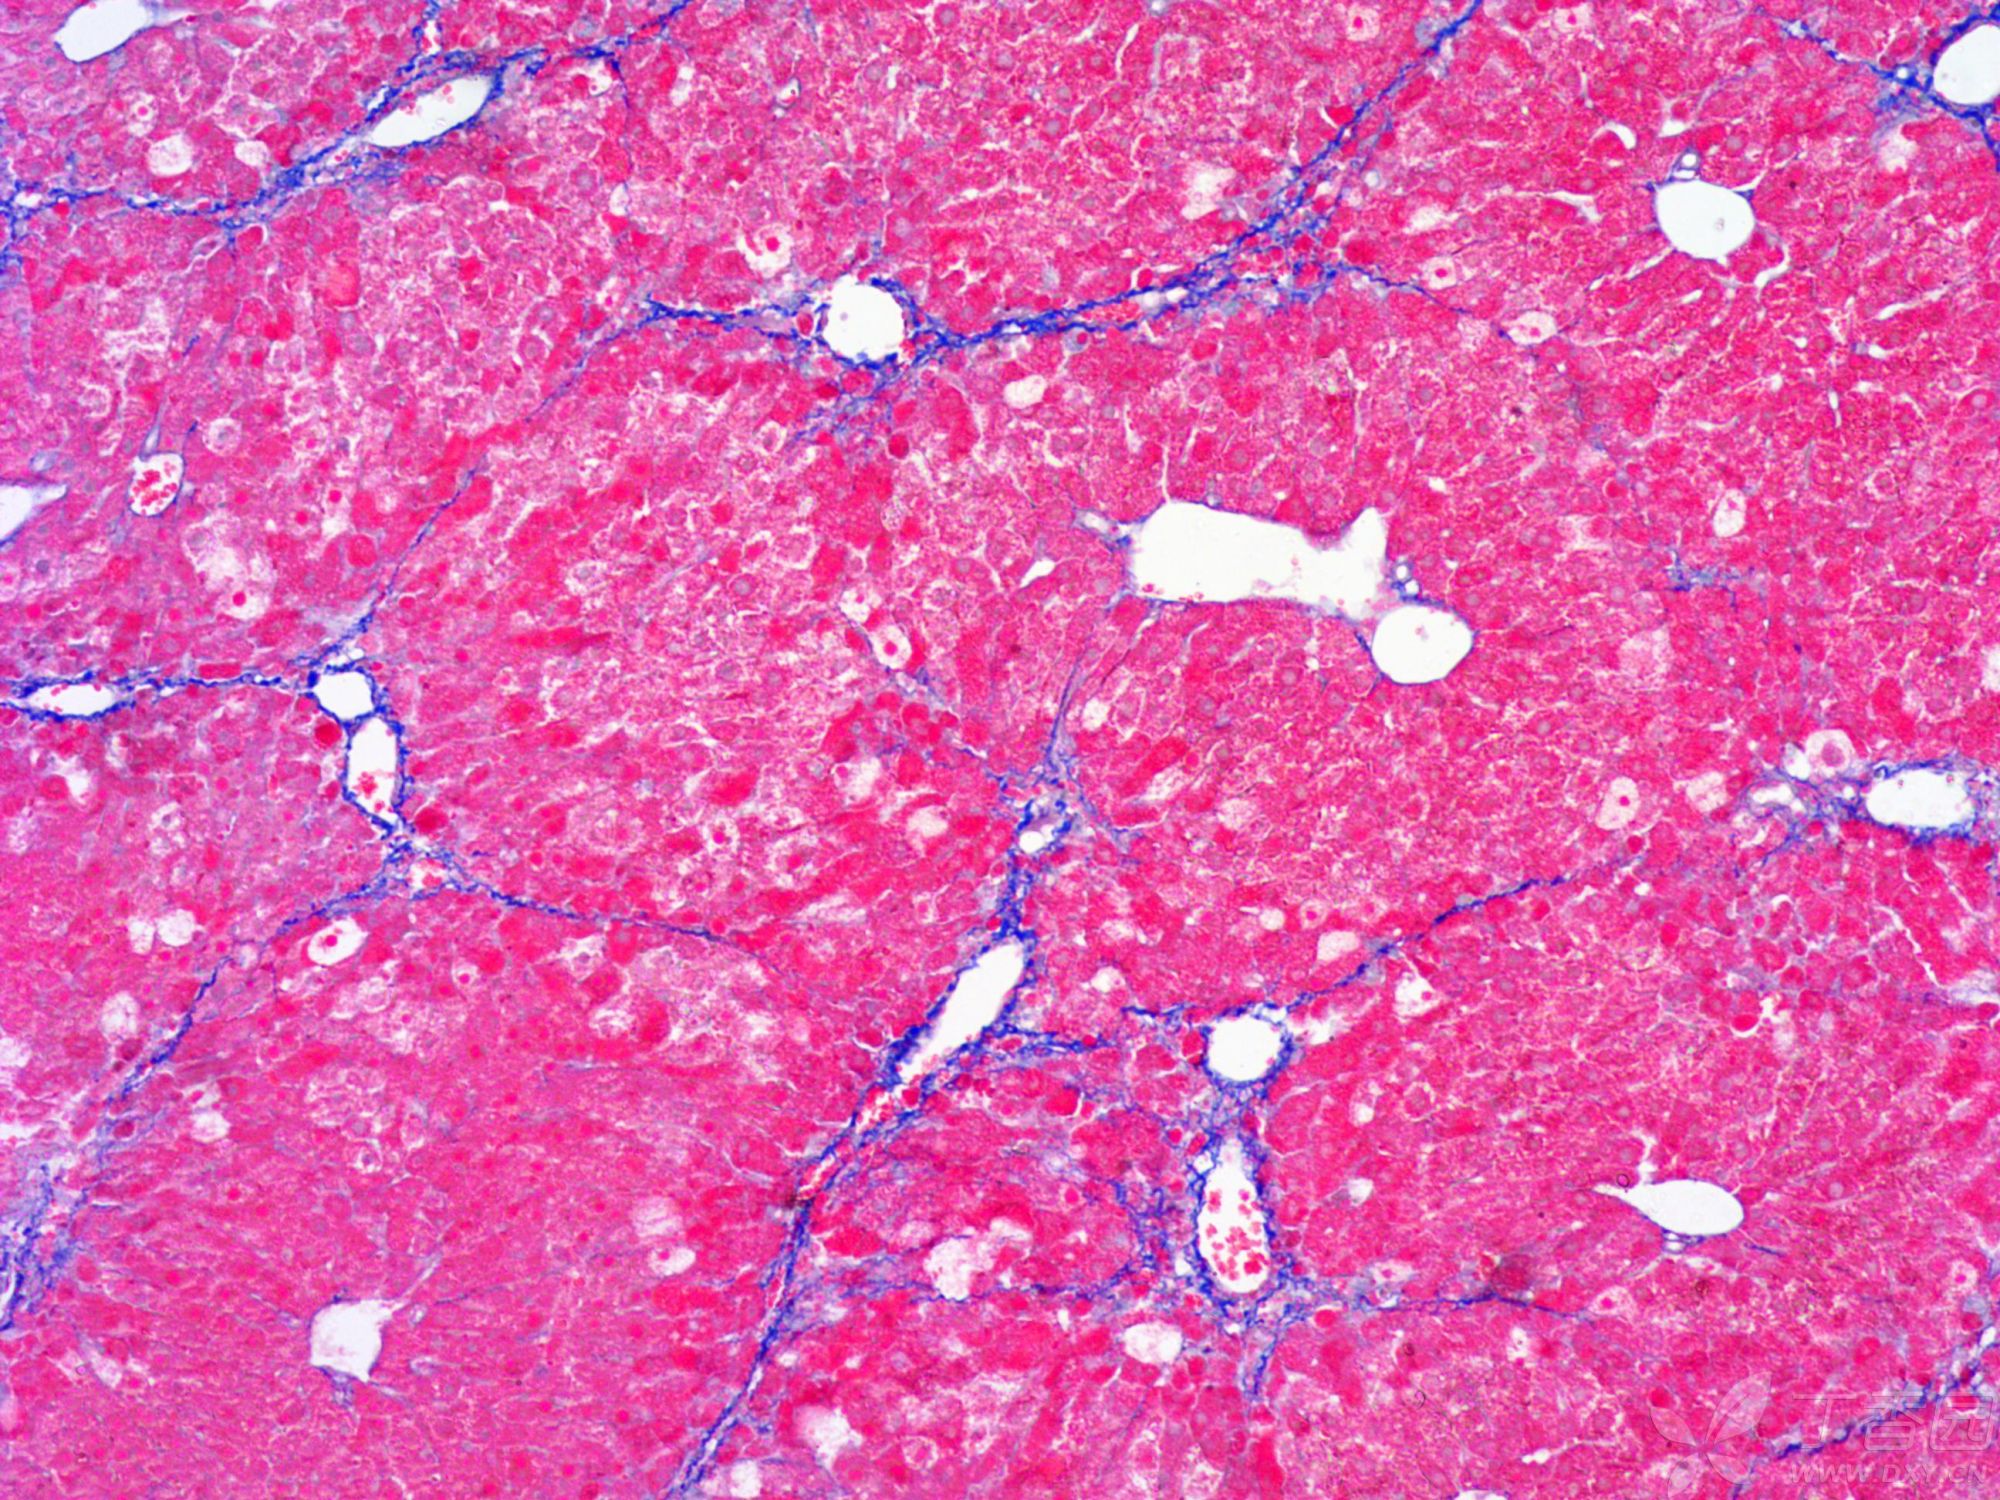

小鼠纖維化

總之,MASSON染色是一種重要的組織學染色方法,通過其獨特的染色原理和步驟,可以實現對組織纖維結構的清晰展示和深入分析。在實際應用中,MASSON染色為醫學研究和臨床診斷提供了有力的支持。